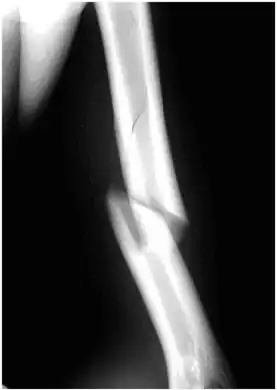

Internal rotation view showing a spiral fracture at junction of middle and distal thirds of humerus.